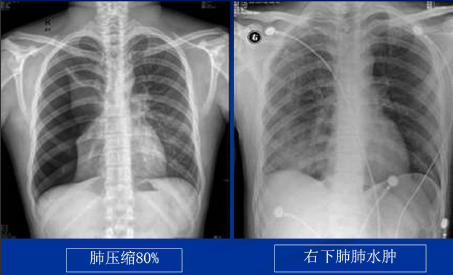

不同类型肺水肿的CT表现(上)

不同类型肺水肿的CT表现(下)